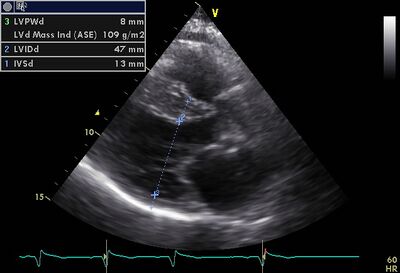

EPSS01.jpg

EPSS is a useful measurement to follow up DCM